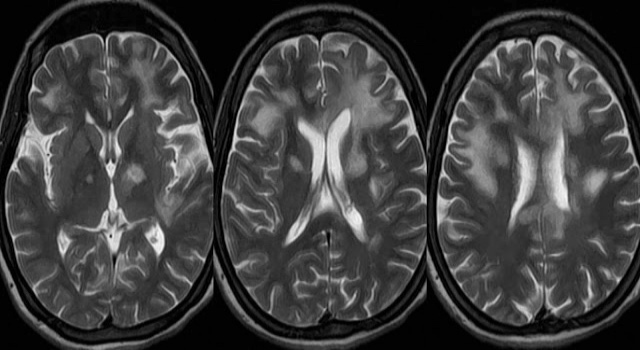

Информация о диссеминированном рассеянном энцефаломиелите